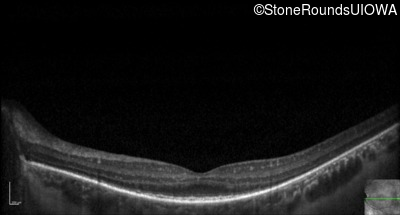

Optical Coherence Tomography - Right - 20/32 -1

Exemplar / OCT Stack

OCT Stack